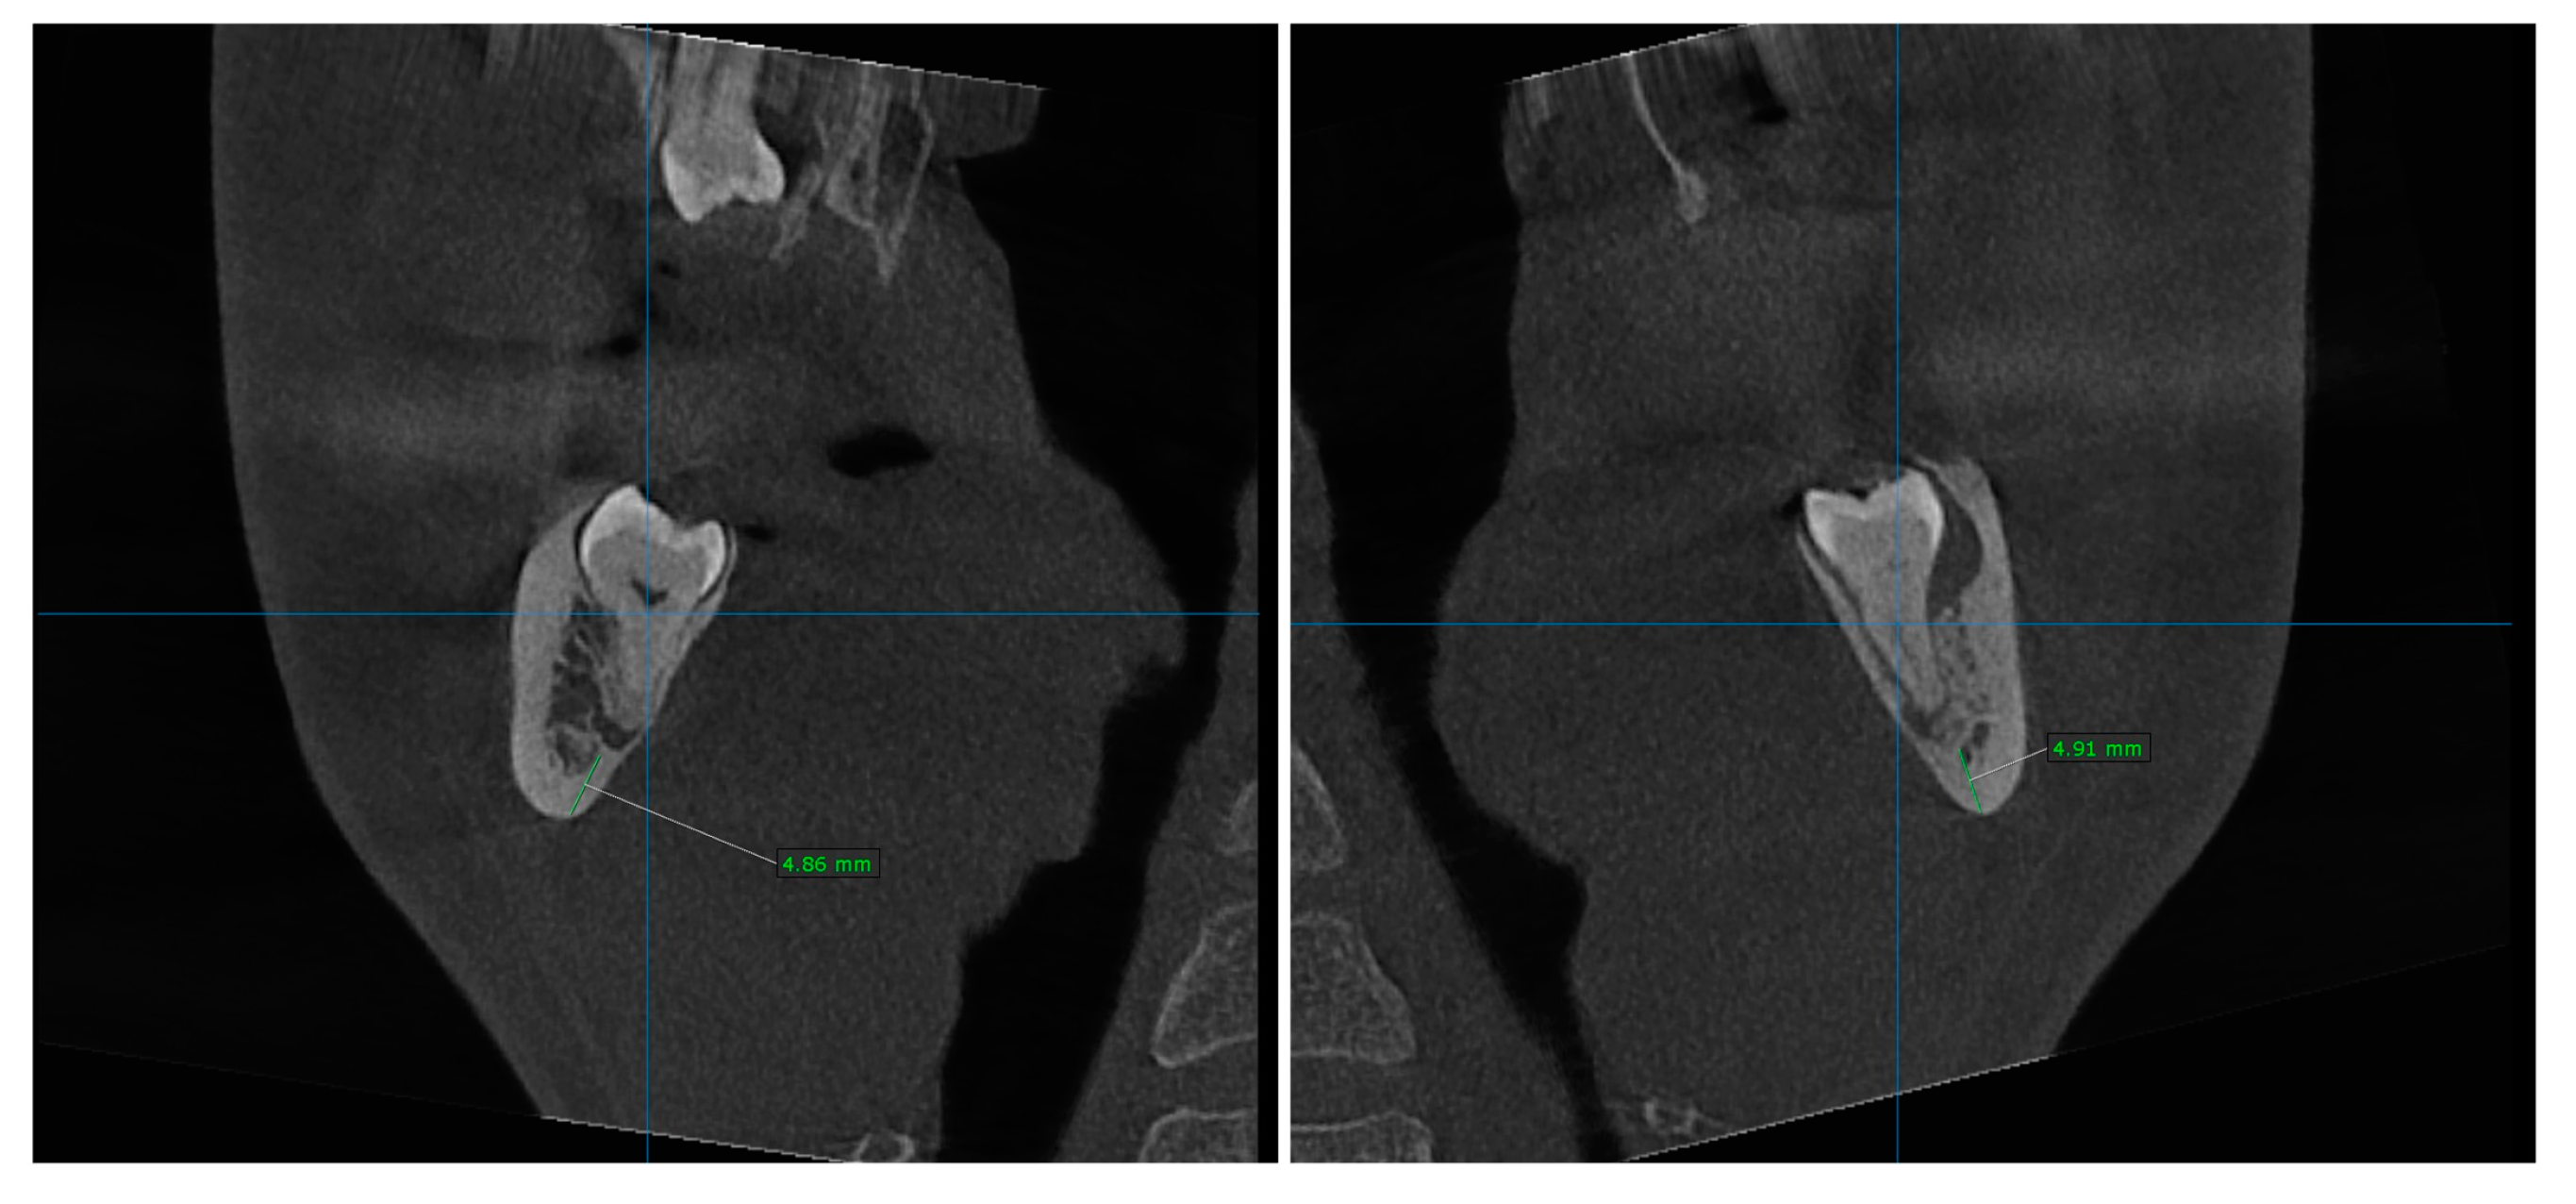

2.2. Pre-Surgical Cone Beam Computed Tomography (CBCT)